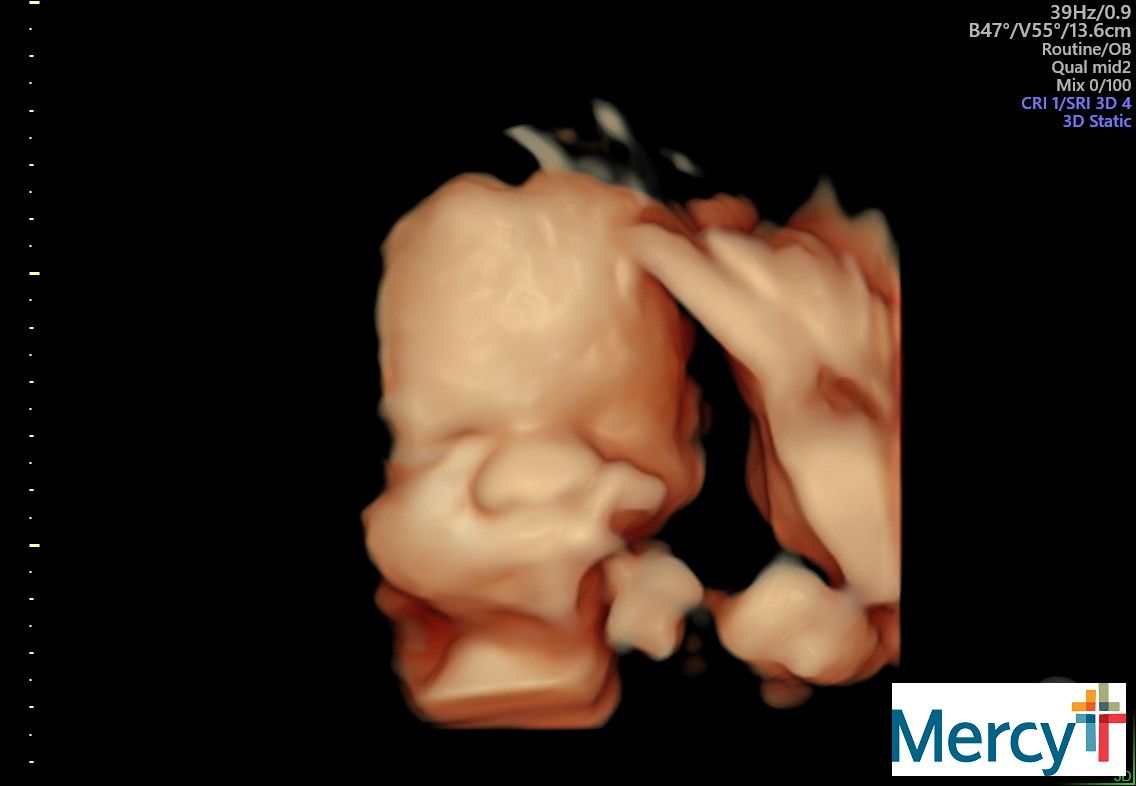

At 32 weeks my appointments would change from once a week to twice a week. These appointments would have a NST (non-stress test) and an ultrasound to check my anniotic fluid levels.

Lupus pregnancies are so complex. The placenta ages rapidly near the end and risk for stillbirth is so high.

She was giving me some more instructions from my MFM doc, and mentioned that because of the high monitoring I needed to be ready to have this baby any time after 34 weeks.